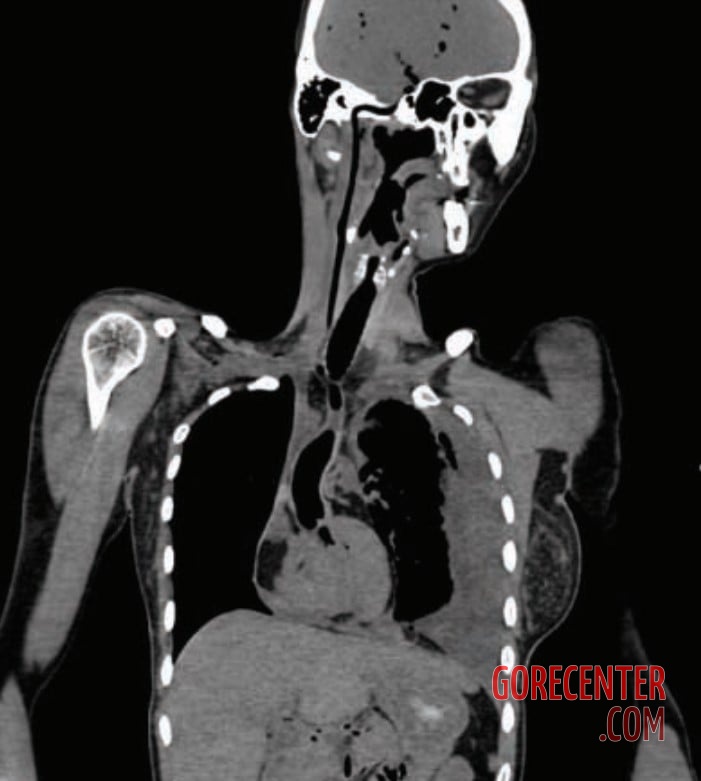

Photos taken during a forensic autopsy show a 41-year-old woman who died as a result of a stab wound to the heart. During an escalated argument, her husband grabbed a knife in a fit of rage and killed her with a single stab. The blade penetrated into the left ventricle, leading to a large accumulation of blood in the pleural cavity and the pericardium.